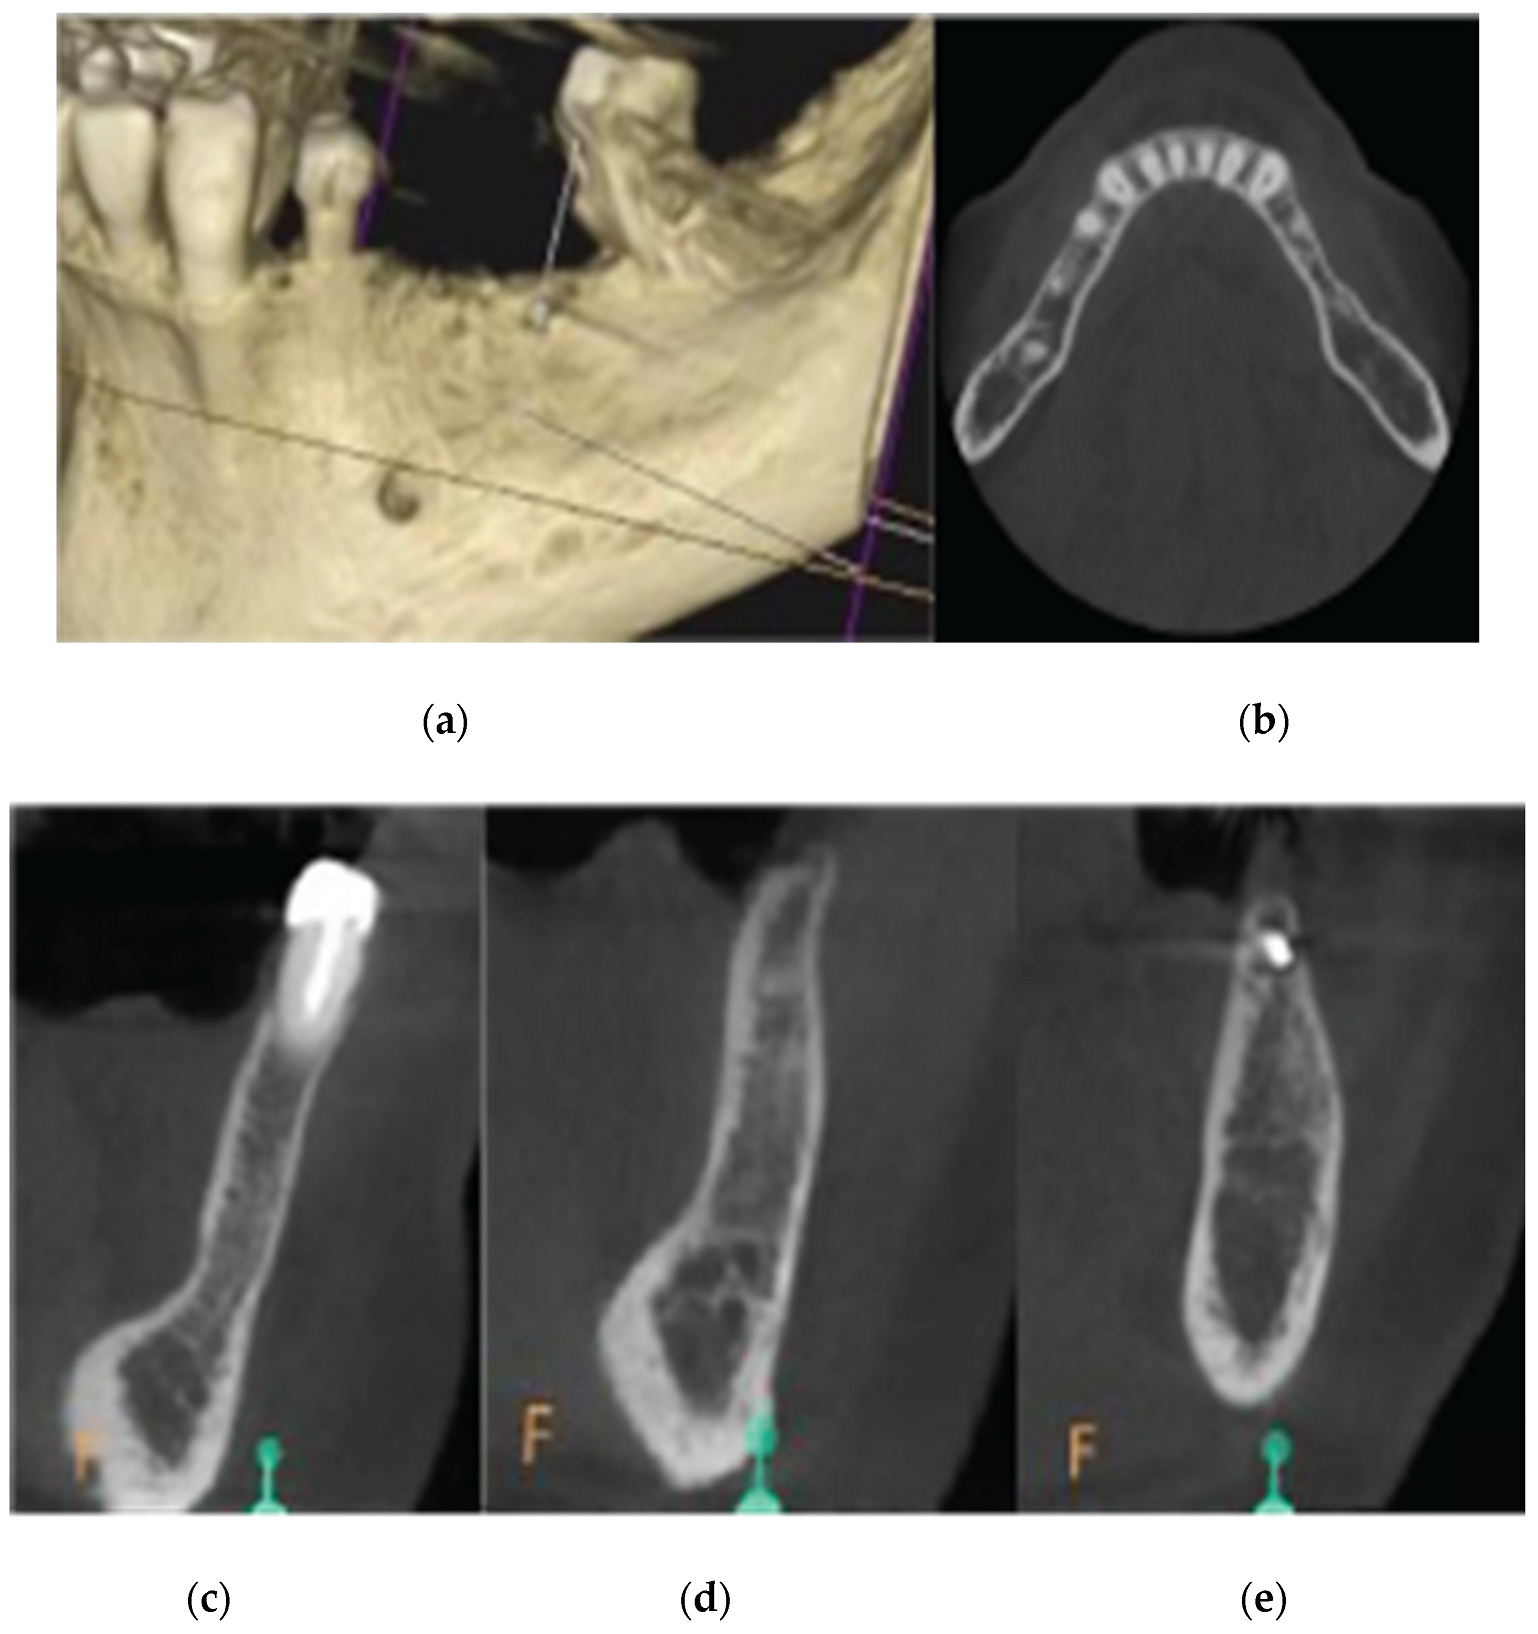

Figure 16. Preop CBCT Situation – (a) 3d representation of the defect, (b).Axial mandibular image. (c) Cross sectional images sites 34, (d) site 35, (e) site 36.

A 68 year old female patient attended our clinic and requested a fixed solution for the posterior edentulous 35-36 area of quadrant 3. The patient was a healthy non-smoker without active periodontal disease (no attachment loss, pockets on probing and BoP). A pre-op Cone Beam Computed Tomography (CBCT) was performed on the lower third quadrant. The results revealed an important horizontal atrophy of the ridge at the area from the distal aspect of the 34 tooth element till the mesial aspect of 38 wisdom tooth. Bone density was defined as type 3 and the distance from the most coronal edge of the alveolar ridge to the inferior alveolar canal was enough to place dental implants (more than 10mm). Residual endodontic filling material within the bone structure was identified on area 36. A periapical lesion apically of 38 roots with underfilled root canal treatment and bone loss at the furcation area was also noted (Figure 16).

Data Collection

CBCT images were obtained using a CS8100 3D Carestream computed radiography system (Carestream Health, USA), at 0,150mm voxel size and field of view 8x9 cm prior (T1) and 16 weeks (T2) after implant placement. The original files in -DICOM format- were imported into the Romexis software (Planmeca Oy, Tuusula, Finland) for analysis. Both T1 and T2 datasets were superimposed in the software, using a point-based registration and if needed further manual alignment by an experienced oral imaging specialist. 2D measurements were acquired on both registered volumes where a slider tool could help hide and show the second superposed volume. First, measurements on T1 were done, after on T2. The cross-section in the middle of the site on the axial slice, and perpendicular to the alveolar crest was used to measure alveolar widths at 1mm, 3mm and 5mm heights (Figure 21, 22). An approximate Bone volume segmentation of the bone gain was performed on both volumes using a manual segmentation tool to visualize the gain in 3D (see Figure 23).